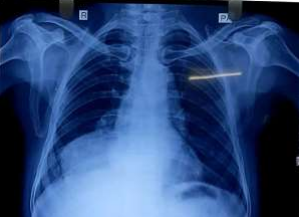

In the subsequent visit, his cough was persisted though fever subsided. His repeat Chest X-ray showed similar right lower lobe dense opacity resembling mass lesion, whereas his sputum reports were negative for M.Tb and sputum culture showed pseudomonas. In suspicion of lung mass, non-contrast CT thorax scan was done and it was found lateral part of ascending thoracic aorta protruded in right lower lobe as aneurysmal sac and surrounded by necrotising consolidation. His sputum was repeated for CBNAAT test and this time found positive for M.Tb, he was started for drug-sensitive Tb regimen and sputum sample sent for M.Tb culture and DST

Fig 2: 2nd Chest X-ray after 10 days

Figure 2